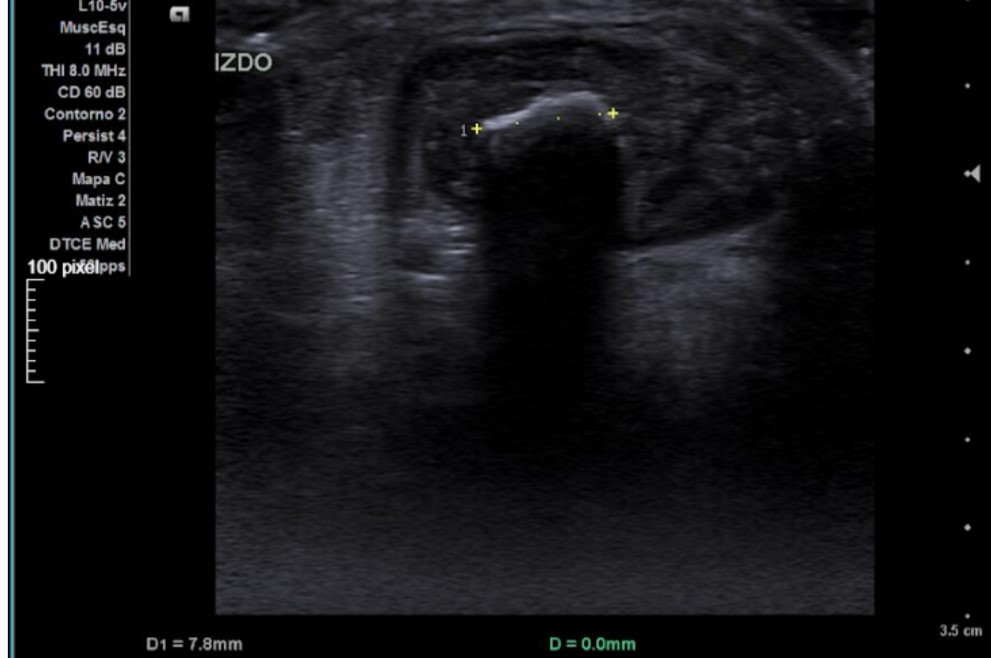

Hallazgos ecográficos

Sonda lineal, corte transversal: engrosamiento de tendón aquíleo izquierdo respecto a contralateral y área hiperecogénica de 7,8 mm con sombra acústica posterior.